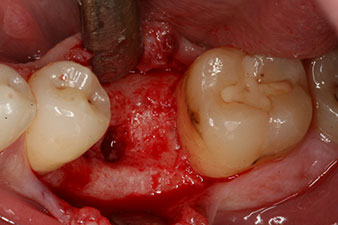

The torque used for the machine-driven placement was 43 Ncm. In addition, after screwing a measuring post (SmartPeg) specially matched to the implant, the ISQ value was measured with the probe of the W&H Osstell ISQ module.

This module is an optional extra for the W&H Implantmed and is docked to the implantology motor (see Fig. 11). The dimensionless ISQ value immediately after insertion was 64 orovestibular and 68 mesiodistal (maximum value = 100).

These values could have indicated open healing or even immediate restoration. Due to the insufficient crestal bone volume at the implant, the region was augmented with the bone chips collected during preparation of the implant bed and sutured to exclude saliva.